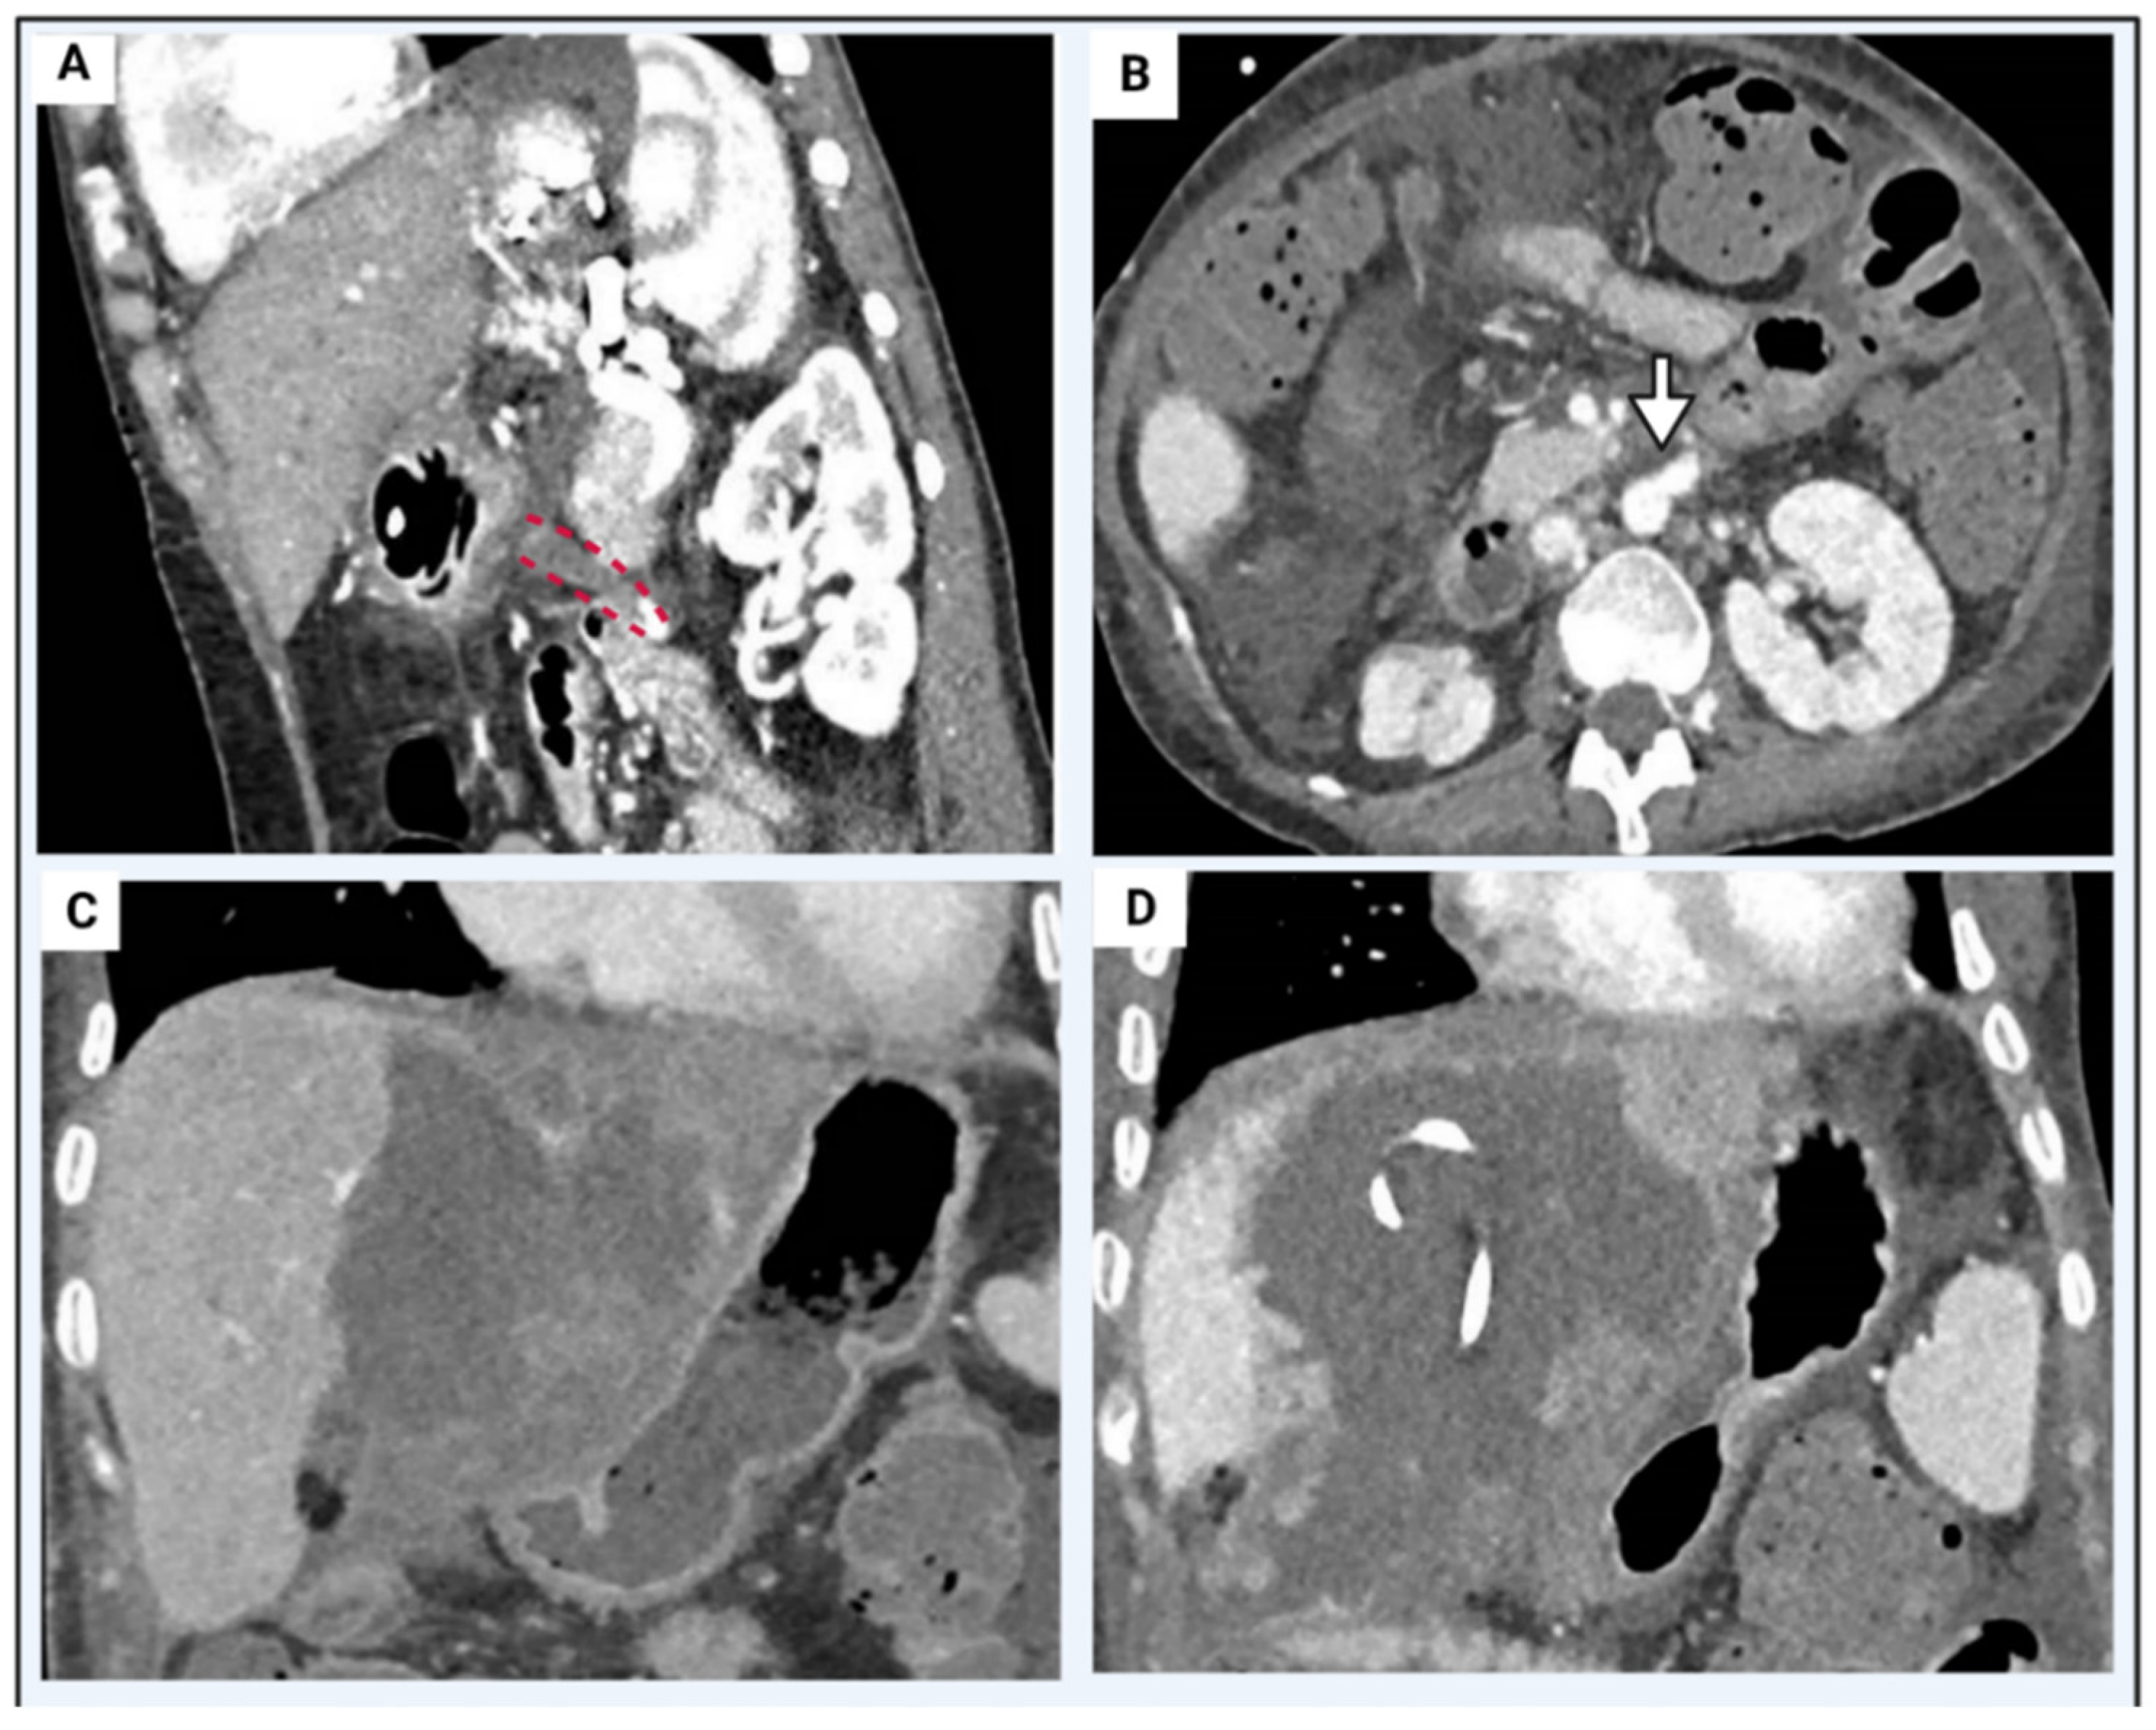

5.3. Portal Vein Thrombosis

| Grade | Extension |

|---|---|

| Grade I | <50% of the vessel lumen with or without minimal extension into the superior mesenteric vein (SMV). |

| Grade II | >50% occlusion of the PV, including total occlusions, with or without minimal extension into the SMV. |

| Grade III | Complete thrombosis of both PV and proximal SMV. Distal SMV is open. |

| Grade IV | Complete thrombosis of the PV and proximal, as well as distal, SMV. |